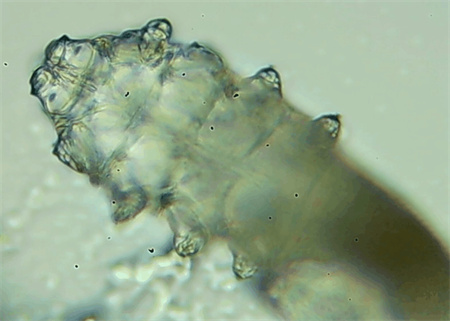

把玻片放到顯微鏡下觀察,通過電腦實(shí)時(shí)傳送的畫面,可以查看到這些拔下來的睫毛上是否有螨蟲。

結(jié)果,有6個(gè)人拔下來的睫毛上都發(fā)現(xiàn)了螨蟲。

這種螨蟲叫做蠕形螨,他們通常呈乳白色、半透明的細(xì)長狀,擁有四對腳。它們跟被子上的塵螨可不是同一種。

這些蠕形螨主要寄生在面部、頭皮、眼睛的睫毛毛囊、睫毛皮脂腺,以及瞼板腺里,以睫毛囊上皮細(xì)胞、腺體內(nèi)脂質(zhì)為食物。因此,即使經(jīng)常換洗床單、衣物,也可能會(huì)有蠕形螨。